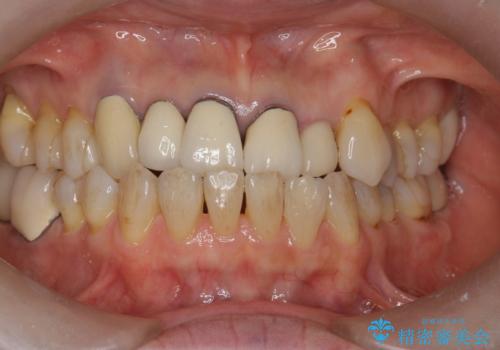

- 60代女性

受け口の程度がある程度あったため、歯軸を無理にかえてかみ合わせを変えると前歯が折れる可能性があるため反対咬合は変えておりません。